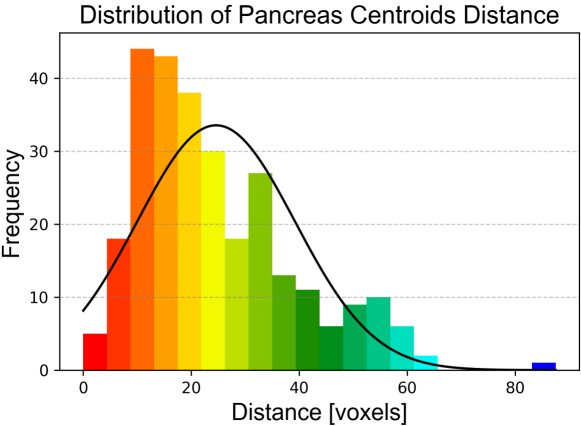

In order to provide an example of the variability of the pancreas parenchyma in terms of size and location, a registration was performed on 281 CTs of the MSD dataset using Elastix software (Klein et al., 2010), adapting inter-subject registration parameters from the study by Qiao et al. (2016) to the CT domain. Subject 29 of MSD was considered a reference image by virtue of its high-quality image and centrality within the range of variations observed in the dataset. A Hounsfield unit (HU) from 100 to 500 was used for all the images to improve the registration process, enhancing bones and brighter abdominal structures. The results are illustrated in Fig. 10. A histogram with the frequency distribution is shown in Fig. 11. It was created by measuring the volumetric distances from the centroid of the pancreas in subject 29 of MSD to the centroids of the pancreas from all other subjects after performing the registration.